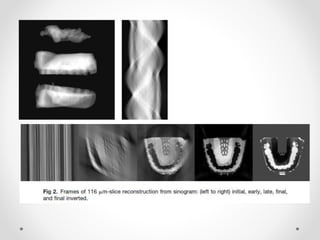

Dentition is prepared by scanning using Orascanner

Structured white light

CBCT scans

• OraScan is intergrated with conventional

photographs and x ray.

• OraScan software

The arch wire geometry is automatically calculated in

three dimension for the bracket positions on the target

arch.

the orthodontist selects the appropriate cross-section ,

material , and force output from the computer menu.

• Orascanner -6 unblured images/sec

3500 3D points per image

accuracy of each point =50 microns

Linear error of scan is .1mm per tooth